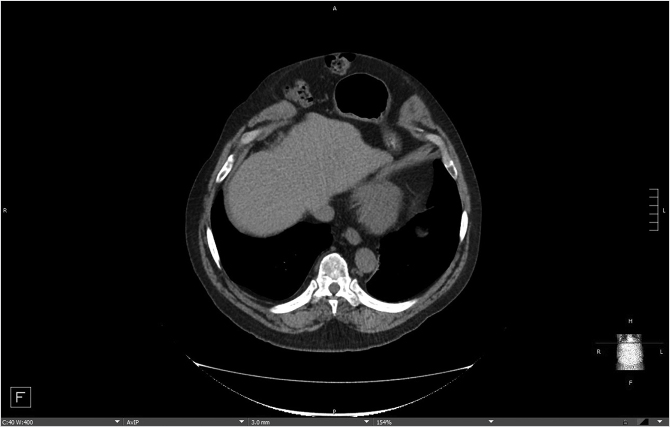

Patient presentation is straightforward, and the majority of diagnoses can be established with a history and physical examination that will distinguish between two conditions—bulges and hernias. Bulges occur when the strength and elasticity of the abdominal wall is not enough to contain the viscera uniformly from episodes of increased intra-abdominal pressure. The classic appearances of postpartum women and the epigastrium of heavier older males (the so-called “beer belly”) are consistent with rectus diastasis and bulges. In general, there is no risk to abdominal wall bulges, because the intestines face a smooth peritoneal lining without abrupt transitions and will not strangulate. In certain areas of the body such as the groin, umbilicus, and the epigastrium, a failure of the local tissue to contain the viscera creates a true hernia–distinctive from abdominal wall bulges due to a small defined ring that can permit entry of a bowel loop and possibly lead to strangulation. In contradistinction to the smooth peritoneal contour of bulges, these “ventral” hernias (as they are located on the front surface of the abdomen) have rings in the shape of the letter omega with a lip that can catch the preperitoneal fat and bowel. A third category of abdominal wall defects is incisional hernias, notable for the scar demonstrating a prior entry into the abdomen (Fig. 41‑1). The scar at the STI has not withstood the abdominal wall tensions and pressures and has failed over time. Mechanistically, the total strength of the physical construct of repair and the biologic healing is less than the loads applied at some point in the postoperative period, leading to deformation of scar and failure. There is some minor overlap between groups; for instance, a bulge from rectus diastasis can be associated with the development of a true umbilical or epigastric hernia. History and physical examination is typically adequate to differentiate these clinical entities, though an abdominal CT scan can add confirmatory information for heavier patients (Fig. 41‑2, Fig. 41‑3).